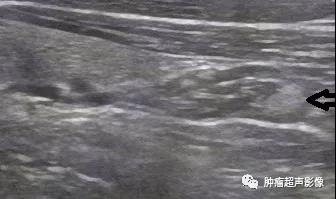

巨大甲状旁腺腺瘤位于甲状腺背侧,形态不规则,完整的包膜,与甲状腺相邻处见双包膜(箭头示),呈低回声,血流丰富杂乱。